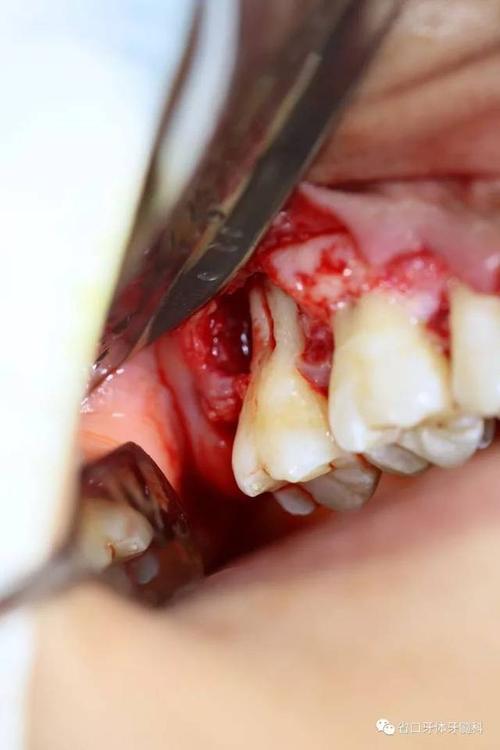

取出牙根,牙槽窝干净无碎屑及肉芽残留.

彻底刮除17根面牙结石和肉芽组织